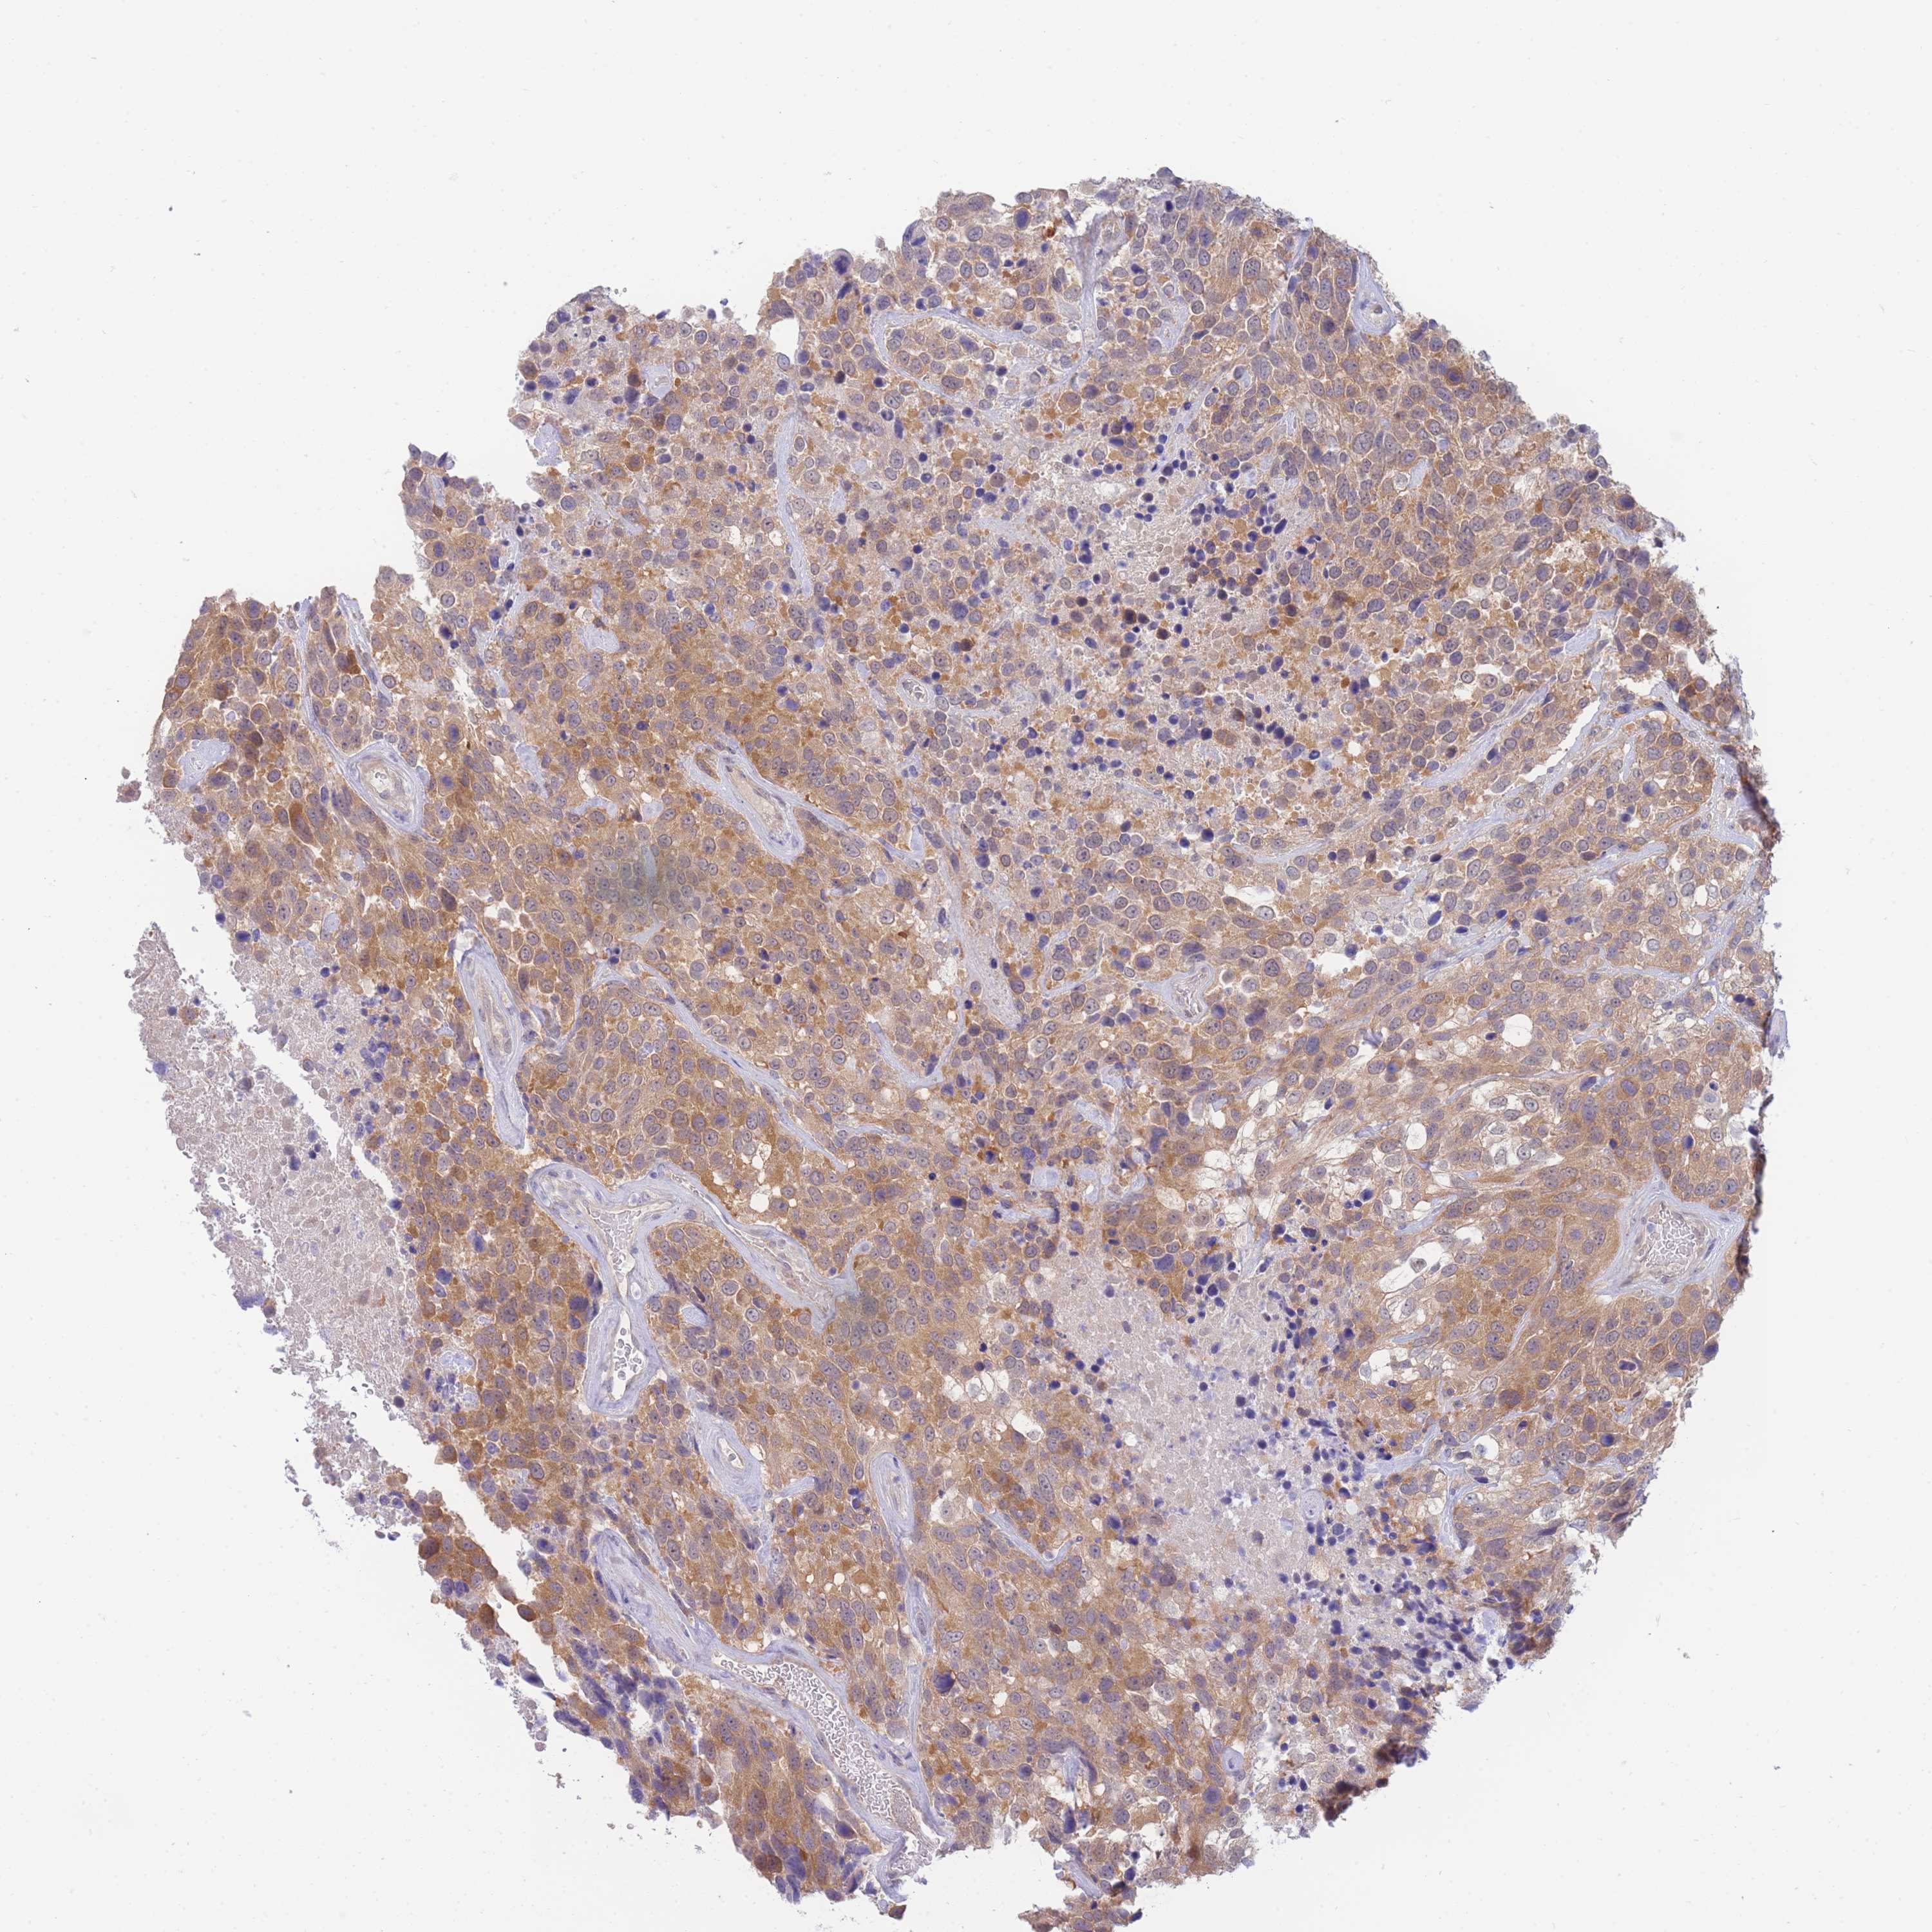

UROTHELIAL CANCER - Protein expressioni

A mouse-over function shows sample information and annotation data. Click on an image to view it in a full screen mode. Samples can be filtered based on level of antibody staining by selecting one or several of the following categories: high, medium, low and not detected. The assay and annotation is described here.

Note that samples used for immunohistochemistry by the Human Protein Atlas do not correspond to samples in the TCGA dataset.

Antibody stainingi

Antibody staining in the annotated cell types in the current human tissue is reported as not detected, low, medium, or high, based on conventional immunohistochemistry profiling in selected tissues. This score is based on the combination of the staining intensity and fraction of stained cells.

Each image is clickable and will lead to virtual microscopy that enables deeper exploration of all samples and also displays staining intensity scores, fraction scores and subcellular localization as well as patient and tissue information for each sample.

Antibody HPA043949

Antibody HPA069215

Antibody CAB015942

Staining

High

Medium

Low

Not detected

Intensity

Strong

Moderate

Weak

Negative

Quantity

>75%

75%-25%

<25%

None

Location

Nuclear

Cytoplasmic/membranous

Cytoplasmic/membranous,nuclear

Urothelial carcinoma, High grade

Urothelial carcinoma, Low grade